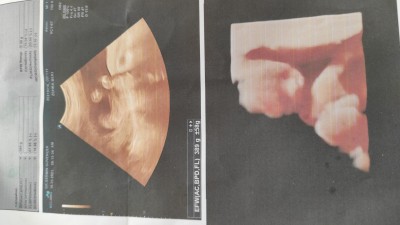

Sizce kilosuna bakilarakta ben kaç haftalık gebeyim ???

Gebelik haftası 27.5

Canım yazılar ölçümler hiç belli olmuyor ki resimde.